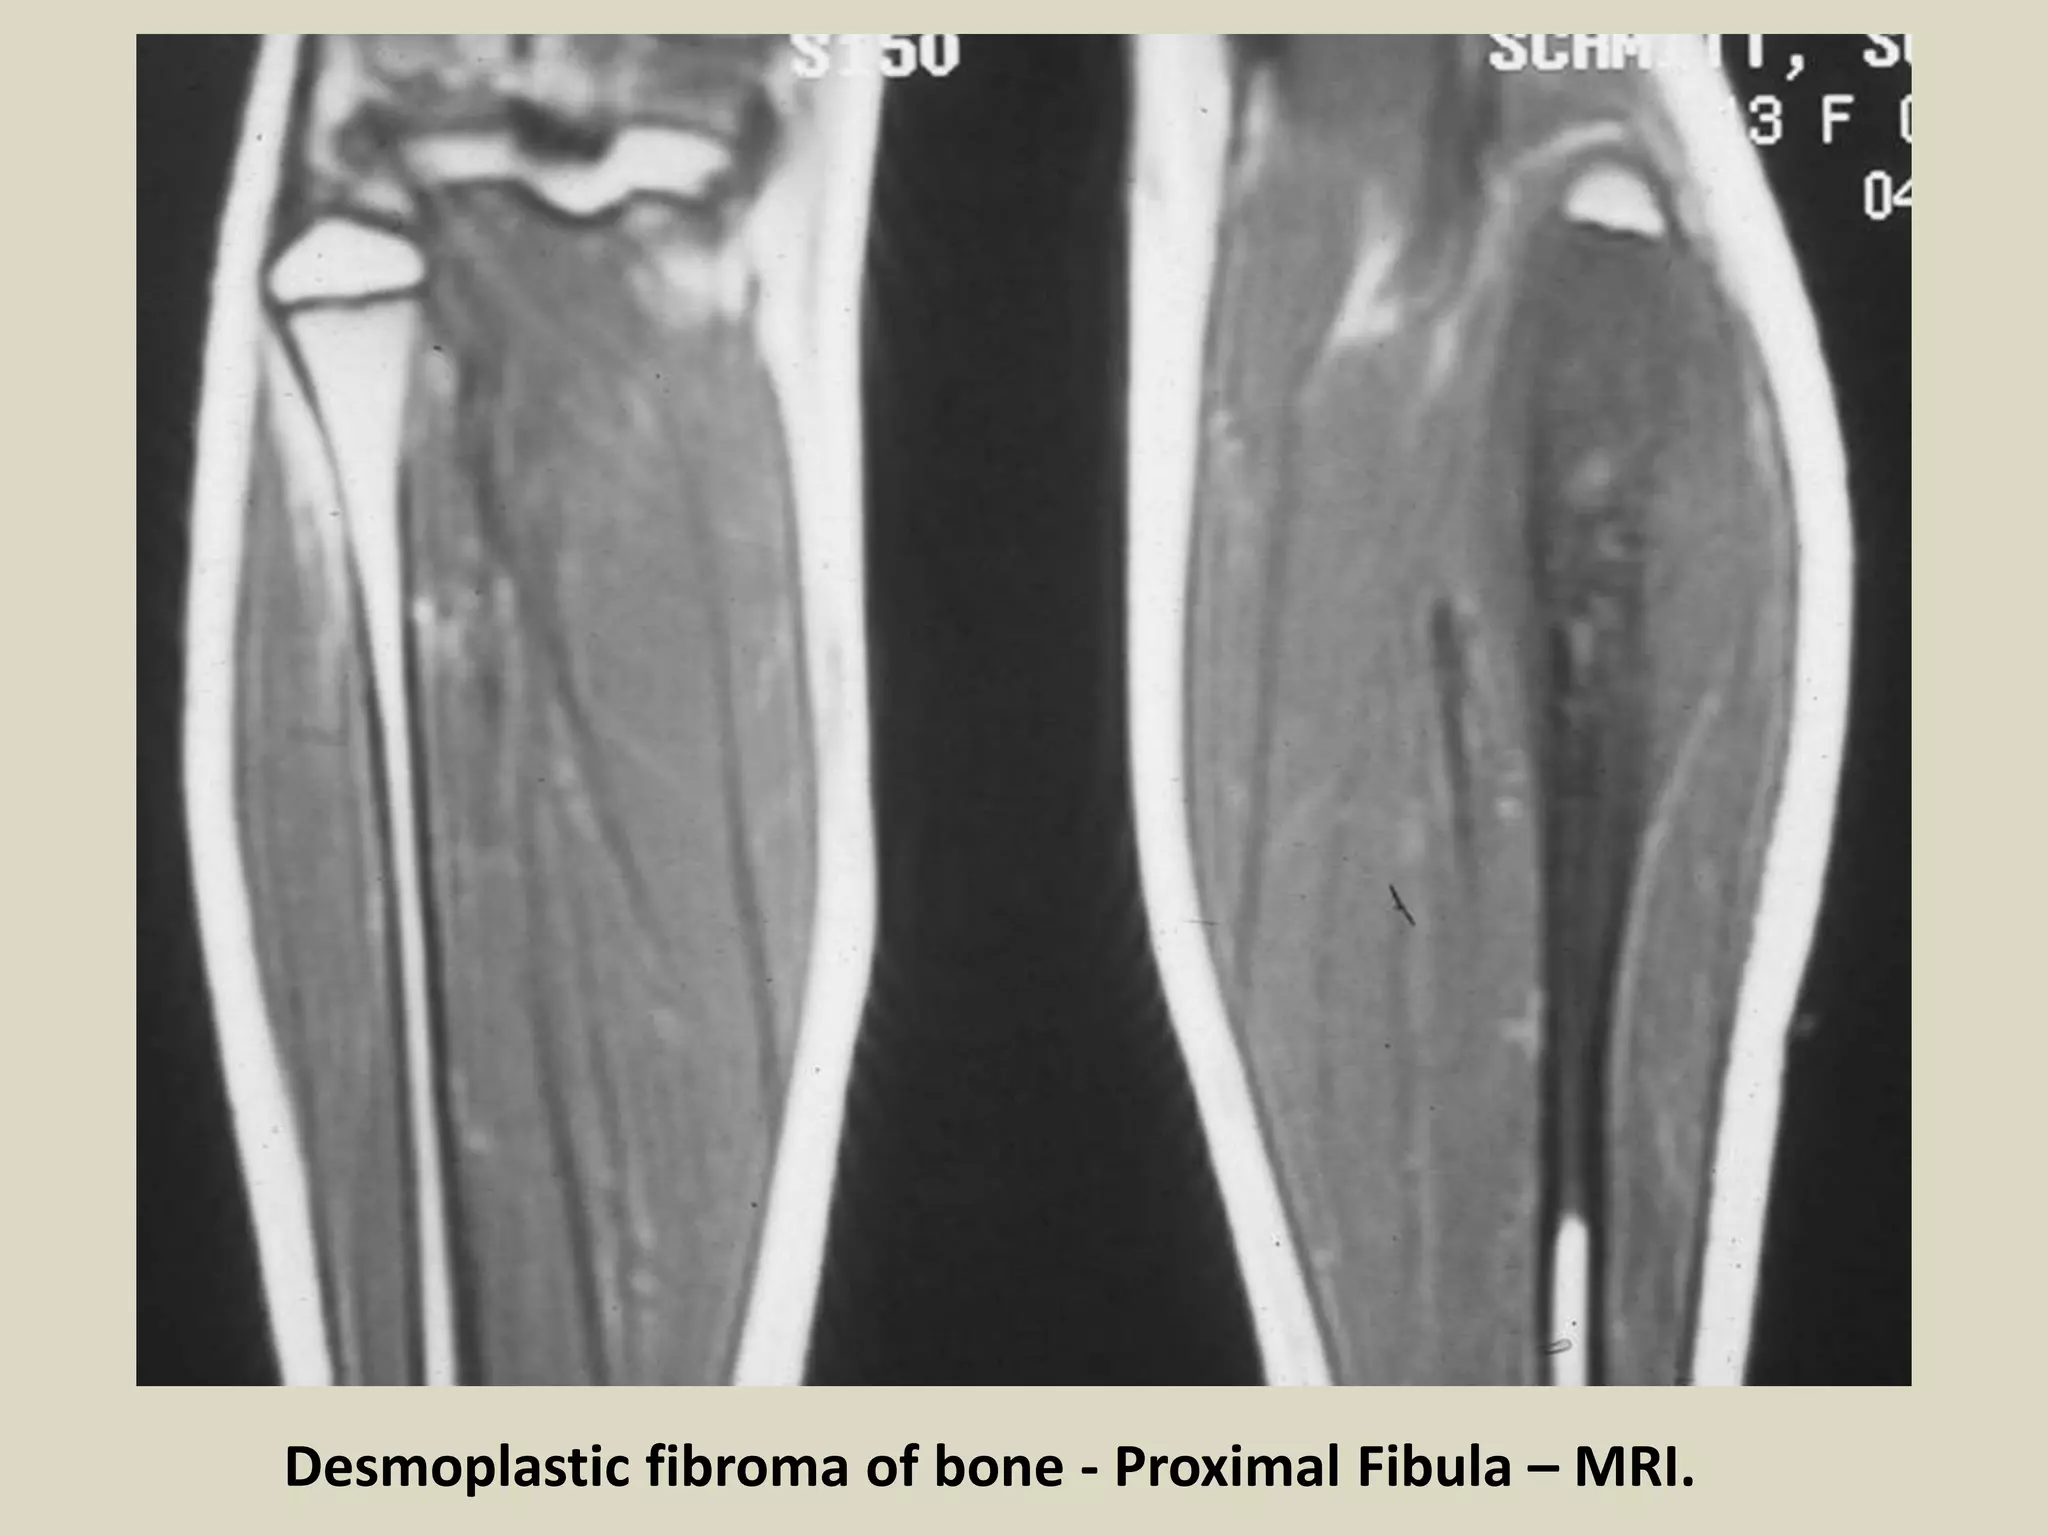

- DF has low signal intensity in both T1 and T2 weighted MRI images.

Desmoplastic fibroma of bone - Proximal Fibula – MRI.